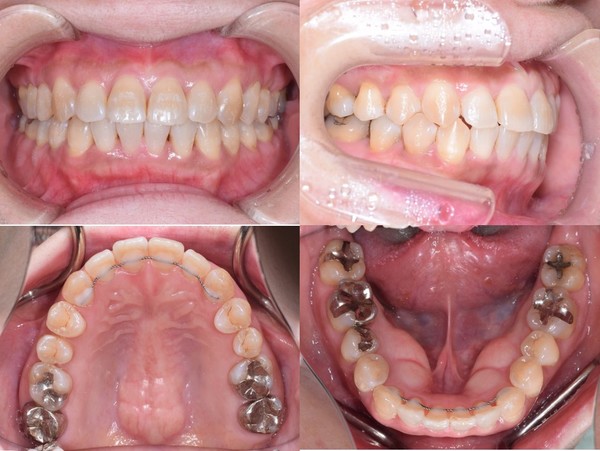

右下3番目の歯が反対になっていることを気にされて、かかりつけ歯科医からのご紹介でご来院 骨格性Ⅰ級右側犬歯反対咬合の診断により、非抜歯、表からのマルチブラケット矯正装置で治療終了

デコボコの歯並びや、反対のかみ合わせが改善されて、機能的にも見ためによくなりましたね(^_^) クリスマスのプレゼント、喜んでいただきありがとうございます♪ 今後も続けていきますよ(^_^)

右側犬歯反対咬合

56歳

唇側マルチブラケット装置

非抜歯

約1年半

約723,000円